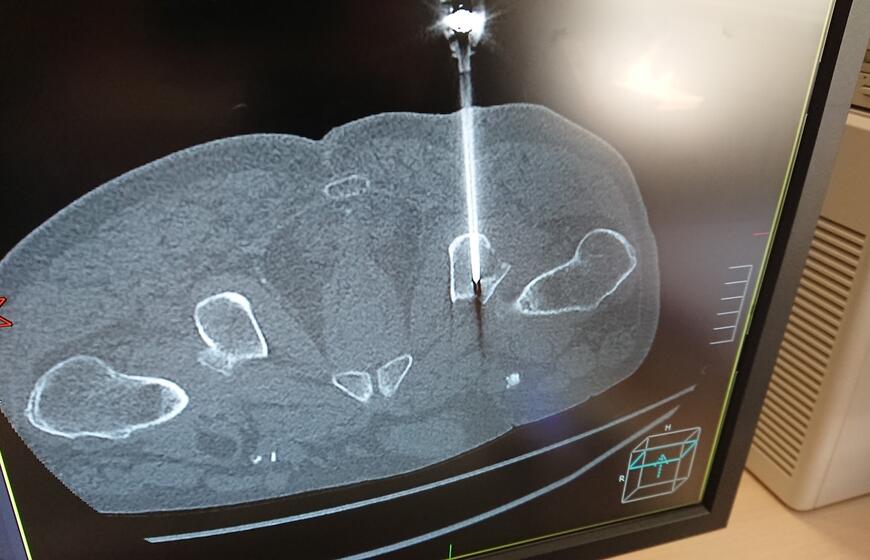

Neurochirurginiam pacientui, nuskausminimo tikslais, Mindaugas Lesutis atliko nervinės šaknelės blokadą stuburo tarpslankstelinėje angoje, o praėjusią savaitę Respublikinėje Klaipėdos ligoninėje pirmą kartą paimta biopsija iš kaulo. Kompiuterinės tomografijos kontrolėje nedidelis kaulo mėginukas buvo paimtas iš įtartino židinio pakitusioje klubo kaulo dalyje. Ši procedūra – minimaliai invazyvi, atliekama vietinėje nejautroje, minimaliais pjūviais, netraumuojant paciento.

„Mes pakankamai dažnai matome pakitimus kauluose, kurių kilmė nėra visiškai aiški ir tik paėmus mėginį galima identifikuoti kas tai per darinys. Tai - vienintelis būdas leidžiantis nustatyti ar darinys yra gėrybinis, ar piktybinis, todėl ši procedūra itin svarbi diagnostikoje“, - sako intervencinis radiologas gydytojas Mindaugas Lesutis.

Minėtu atveju nustatyta piktybinio naviko metastazė, kas leis tinkamai įvertinti paciento būklę ir planuoti atitinkamą gydymą.